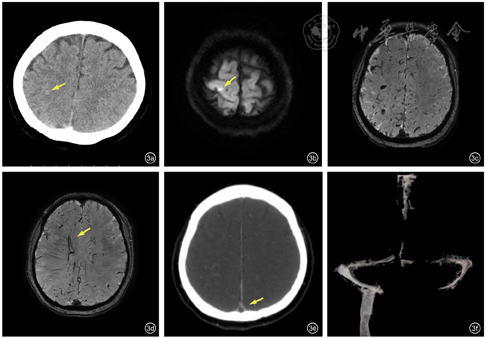

复查颅脑CT:右侧额顶叶多发稍高密度影,出血灶可能性大(图3a)。颅脑MR检查示:右侧顶叶梗死灶可能性大(亚急性期,图3b),双侧额顶叶多发异常信号,为新发,其中T2*加权血管成像(SWAN)序列低信号,考虑微出血灶可能性大(图3c)。另在SWAN序列上可见侧脑室旁多发血管影(图3d)。颅脑CT静脉成像检查示:上矢状窦后部、窦汇(图3e、f)、左侧乙状窦、横窦及左侧颈内静脉显影差,局部充盈缺损,不除外静脉窦血栓形成。患者拒绝数字减影血管造影检查。腰椎穿刺检查示:脑脊液压力250 mmH2O(1 mmH2O=0.098 kPa);总蛋白53.6 mg/dl(15~45 mg/dl),葡萄糖、氯化物、白细胞、抗酸染色、墨汁染色、抗酸杆菌荧光定量多聚酶链反应、病毒五项均正常。脑脊液细胞学未见明确肿瘤细胞。眼底检查未见视乳头水肿。考虑此患者卒中起病为皮层静脉血栓引起出血性梗死所致。患者左侧肢体麻木无力症状在接受腰椎穿刺检查后次日戏剧性消失,未予以抗凝治疗。此后患者停用他莫昔芬,随访4年未再出现血栓事件。

病例2为中年女性,急性起病,以眩晕为首发症状,随后出现一侧肢体无力、麻木。颅脑MR检查可见右顶叶出血性梗死灶及双侧额顶叶散在多发微出血。颅脑CT静脉成像示静脉窦及左侧颈内静脉窦血栓形成可能,而SWAN序列邻近侧脑室周围多发迂曲血管影考虑为代偿血管。患者腰椎穿刺查脑脊液压力为250 mmH2O,恰为临床诊断颅内压增高界限值,眼底检查未见视乳头水肿,故诊断静脉窦血栓继发颅内压增高证据欠充分。结合其局灶神经系统表现及凝血指标异常,最终临床诊断为孤立性皮层浅静脉血栓。颅内静脉血栓包括静脉窦血栓、大脑深静脉血栓及皮层静脉血栓3类,以静脉窦血栓最为常见。皮层静脉血栓临床表现往往缺乏特异性,可表现为头痛、呕吐、局灶性神经功能缺损、癫痫、意识障碍等,MR影像可见近皮层病灶。由于病变为小血管的分支,MR静脉成像及CT静脉成像多无异常发现。数字减影血管造影可见静脉部分或完全缺损,甚至也可无阳性发现。本病一般存在诱因,多与高凝状态有关[14]。该患者有乳腺癌病史及他莫昔芬用药史,可能存在两种引起高凝状态的机制。由于其肿瘤病情相对稳定,进而推测他莫昔芬导致的高凝状态诱发皮层静脉血栓为主要原因。患者既往应用他莫昔芬后出现左侧腘静脉血栓,更支持其对该药所致高凝状态易感。他莫昔芬为非类固醇类抗雌激素药物,用于雌激素受体阳性乳腺癌患者的内分泌治疗,其通过与雌激素受体结合,抑制雌激素促肿瘤增殖作用。研究发现,他莫昔芬可通过影响蛋白C、蛋白S、抗凝血酶Ⅲ的活性而引起高凝状态,增加血栓事件发生风险[15]。他莫昔芬促凝继发的血栓事件主要累及静脉,也可累及动脉。除了作用于肢体大血管,也可发生于心、脑、肝等重要脏器血管。治疗上主要采取低分子肝素及华法林抗凝、rt-PA或尿激酶溶栓以及手术切除血栓。同时,在评估患者肿瘤原发病的前提下,停用他莫昔芬,或应用芳香化酶抑制剂如阿那曲唑替代。具体个案报道[16, 17, 18, 19, 20, 21, 22, 23, 24, 25, 26, 27, 28, 29]汇总见表2。